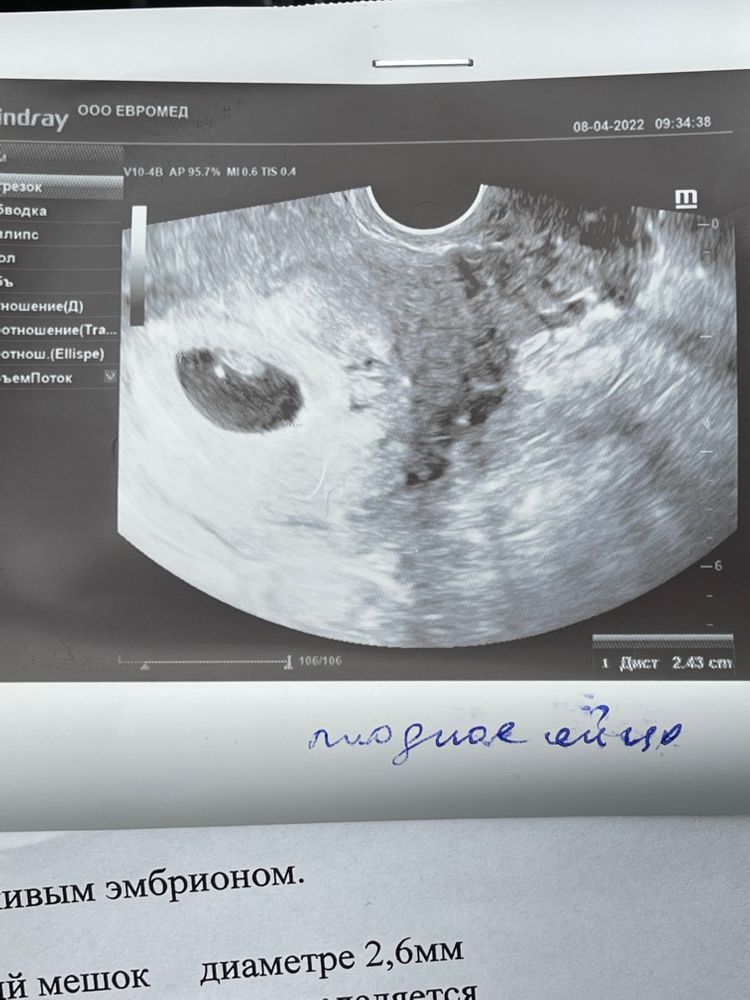

Первое узи в 6,4 недели

Сходила на узи. Все у нас хорошо, крупняши мы🥰 наверное мальчик будет, у меня всегда сыновья на неделю-две опережали срок.